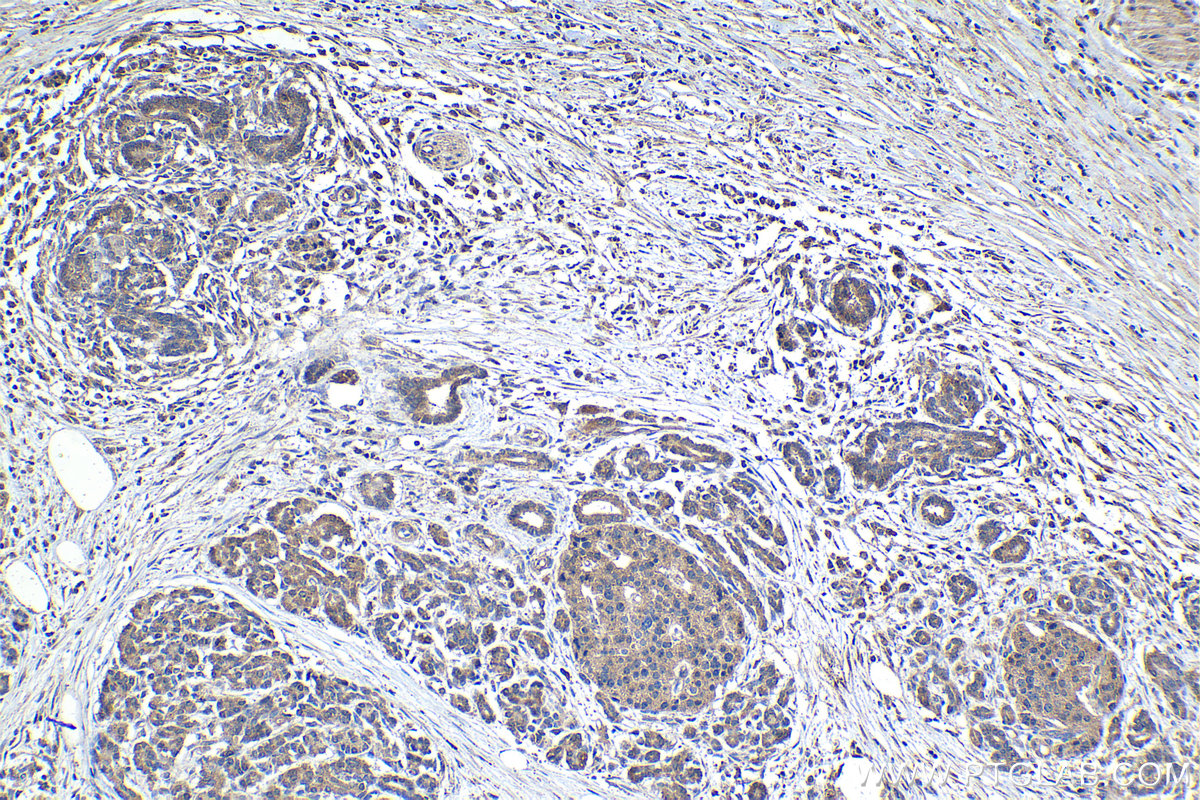

Immunohistochemical analysis of paraffin-embedded human pancreas cancer tissue slide using 21146-1-AP (LARS antibody) at dilution of 1:1000 (under 10x lens). Heat mediated antigen retrieval with Tris-EDTA buffer (pH 9.0). Multi-rAb™ Polymer HRP-Goat anti-rabbit Recombinant secondary antibody RGAR011 was used for detection.

Immunohistochemical analysis of paraffin-embedded human pancreas cancer tissue slide using 21146-1-AP (LARS antibody) at dilution of 1:1000 (under 40x lens). Heat mediated antigen retrieval with Tris-EDTA buffer (pH 9.0). Multi-rAb™ Polymer HRP-Goat anti-rabbit Recombinant secondary antibody RGAR011 was used for detection.